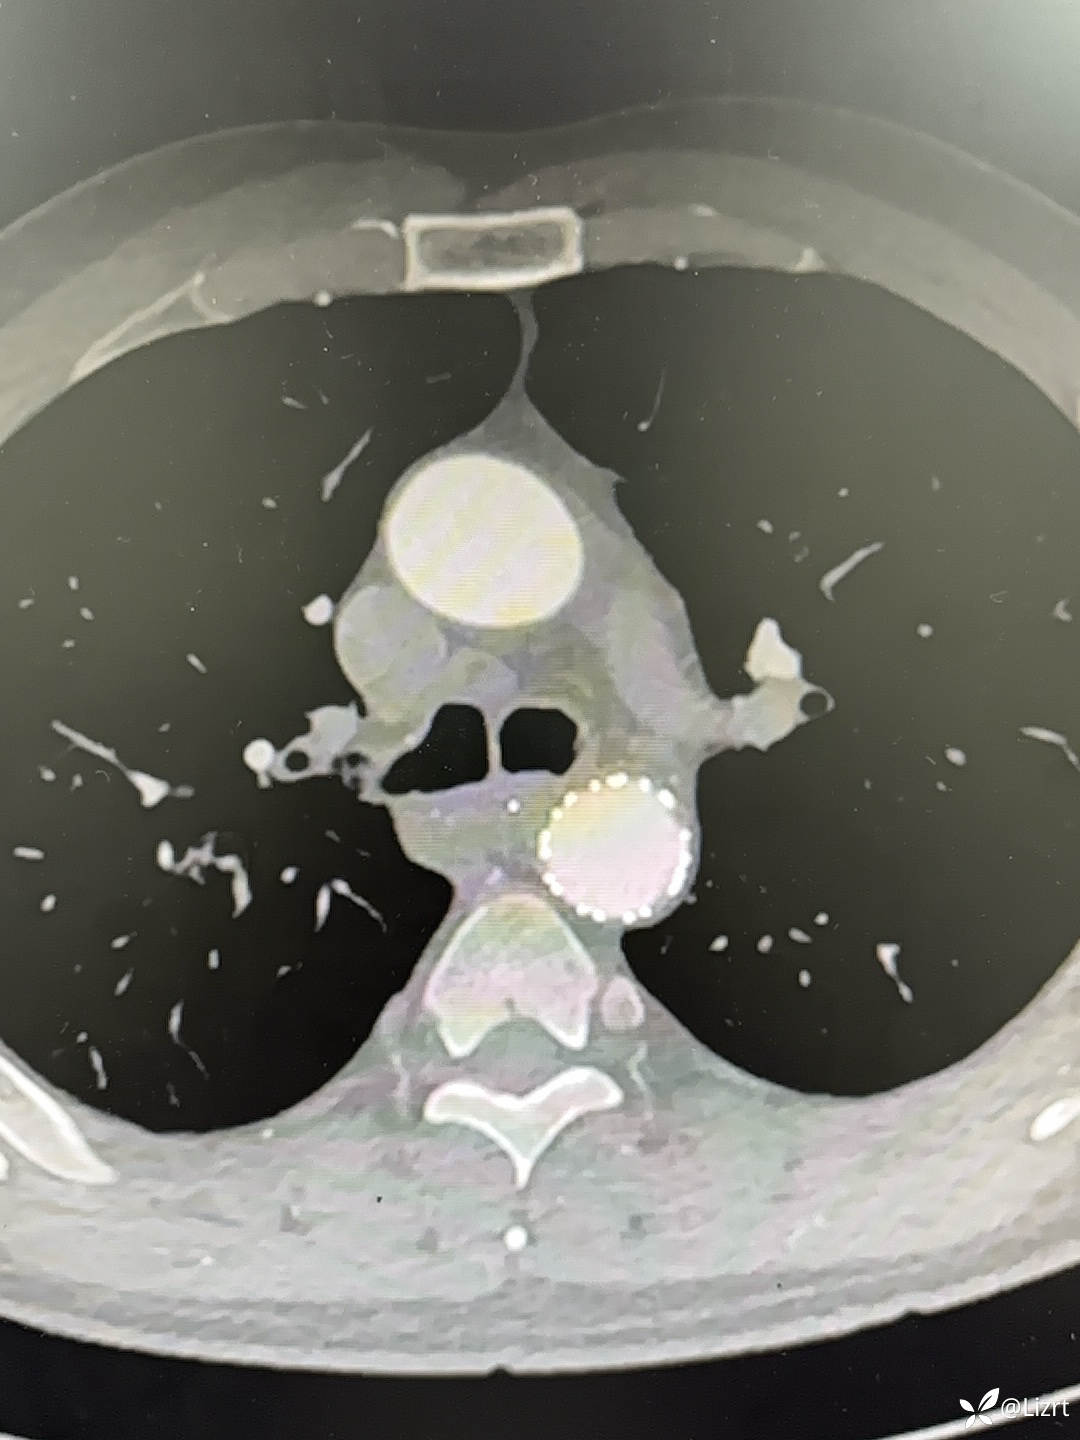

术后2周,复查胸腹主动脉CTA,胸主动脉支架在位通畅。

胸腹主动脉CTA三维重建